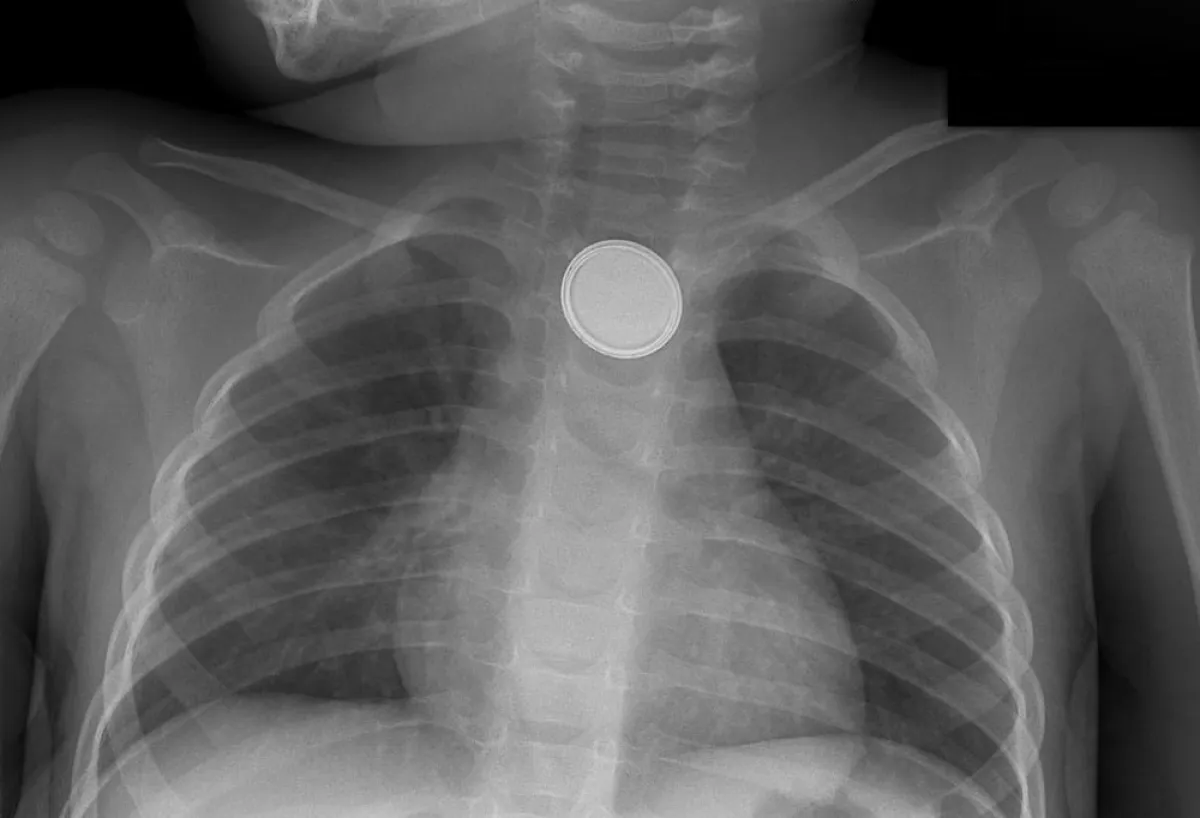

١- توقف القطعة في المريء

العلاج: إجراء منظار للمريء تحت المخدر العام لإزالة القطعة، وفي حال أن القطعة نزلت إلى المعدة، ننتظر عليها قليلاً، وإذا تجاوز الجسم المبلوع المريء فلا داعي للعجلة ففي الغالب يخرج مع الفضلات، لكن يجب التدخل في حالات ابتلاع جسم حاد كالإبرة والدبوس، أو بلع بطاريات خصوصاً إذا لم يتحرك الجسم من مكانه لأكثر من أسبوعين.

كما أن هناك حالات خاصة وخطيرة، وهي البطاريات بكل أنواعها سواءً بطاريات الساعات أو البطاريات العادية نظراً لوجود شحنات كهربائية، وتسرب مادة البطارية فإنها تحدث ضرراً بالغاً في جدار المريء والقصبة الهوائية؛ مما يسبب تلفاً، أو قد يسبب ناسوراً بين القصبة الهوائية والمريء، وعلاج هذه المضاعفات يتطلب عدة أسابيع، وأحياناً أشهراً من التنويم في المستشفى.